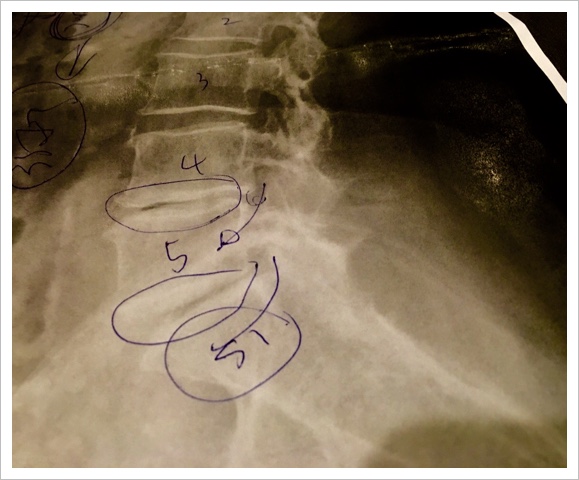

°ÊÁ°¤«¤é¹ø¤Î£´ÈÖ£µÈÖ¤Î´Ö¤ÎÆð¹ü¤¬¤¹¤ê¸º¤Ã¤Æ¤ª¤ê¡¢¤ä¤Ï¤êº£Æü¤Î¥ì¥ó¥È¥²¥ó¤Ç¤âƱ¤¸·ë²Ì¡¢·ë¶É(¶¹ºõ¾É)¤È¤Î¿ÇÃǤǤ·¤¿¡£

¶¹ºõ¾É¤È¤¤¤¦¿ÇÃǤǤ·¤¿¡£

¤â¤È¤â¤È¤¹¤ê¸º¤Ã¤Æ¤ª¤ê¤Þ¤·¤¿4ÈÖ¡¢5È֤ˡ¢Â¼ó¤Î¹üÀÞ¡¢¥ê¥Ï¥Ó¥ê¡¢Âౡ¸å¤ÎÀ¸³èÅù¡¢¿§¡¹¤Ê»ö¤¬½Å¤Ê¤ê¹ø¤ËÉéô¤ò¤«¤±¤¹¤®¤¿¤Î¤Ç¤Ï¤È»×¤¤¤Þ¤¹¡£

ºòÆü¡¢¼ê½Ñ¸å¤ÎÄê´ü¿ÇÎŤΤ¿¤áɱ¡¤Ø»²¤ê¤Þ¤·¤¿¡£¤½¤Î»þº£¤Î¾õ¶·¤ò¤ªÏä·¤·¤Æ¡¢¥ì¥ó¥È¥²¥ó¤ò»£¤Ã¤Æ¤¤¤¿¤À¤¤Þ¤·¤¿¡£

·ë²Ì¤ÏƱ¤¸·ë²Ì¤Ç¤·¤¿¡£